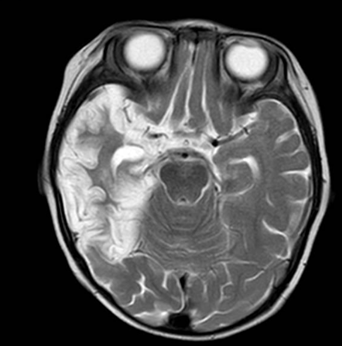

图1 单纯疱疹病毒脑炎,箭头所示为颞岛叶皮层坏死、脑软化及部分胶质增生